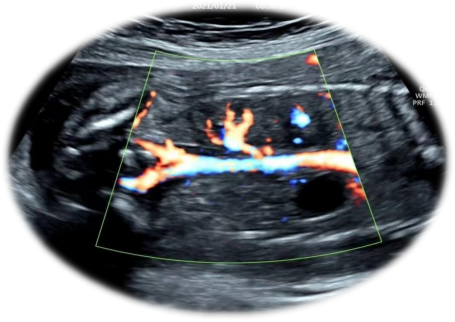

单侧肾缺如的超声表现:

3.彩色多普勒超声显示缺如侧肾动脉亦缺如。

超声科医生在诊断单侧肾缺如时都非常谨慎,需要非常仔细地检查腹腔内尤其是盆腔内有无异位肾存在,才高度怀疑单侧肾缺如。